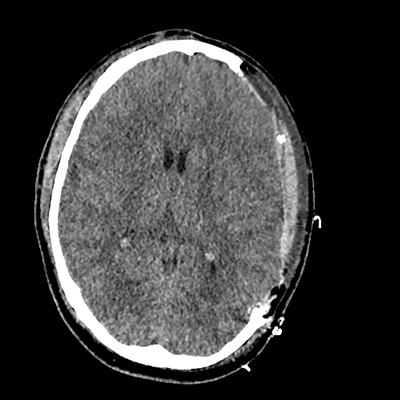

On day 5 of admission, he begins having intracranial hypertension again, spiking up to 40mmHg. You bolus with propofol and fentanyl, to no avail. You then push 30mL of 23.4% NaCl, which provides some brief improvement, allowing you to quickly get a non-contrast head CT. Unfortunately, he's now back up to 36mmHg. You review his labs, and note the following: Na 150, K 3.8, Cl 119, HCO3 18, BUN 21, Cr 0.85, glucose 136, sOsm 320.

NCHCT

NCHCT 3/20 3/20